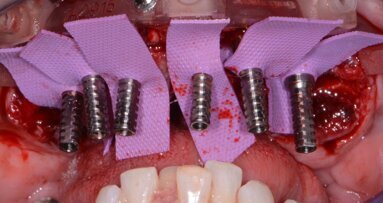

On the day of the surgery, the extraction of the milk and the included canines was made after an intra-sulcular palatal incision from the first upper premolar to the central incisor to allow for a good visibility of the area to treat. The extraction of the canine required a previous osteotomy and the section of the tooth. The socket walls and bone defect were debrided before initiating the drilling for the implant placement (Figs. 3 & 4).

Figs. 3–8: Extraction of the milk and the included canines (Figs. 3 & 4). Implant in final position with palatal bone grafting (Figs. 5 & 6). Impression making for the provisional restoration (Fig. 7). Provisional crown in place (Fig.8).

After a meticulous drilling sequence, a Nano-Tite Prevail Certain implant 4mm in diameter and 13mm in length (BIOMET 3i, Inc.) was slowly inserted with the drill unit at 40 Ncm torque, maintaining the direction of the osteotomy (Figs. 7 & 8). This implant, thanks to its expanded collar shape, is ideal to seal the access to the alveolus, to achieve optimal coronal stability and to preserve the crestal bone thanks to the integrated ‘platform switching’. The palatal bone defect was filled with the bone chips collected from the drilling in a bone filter (Fig. 6).